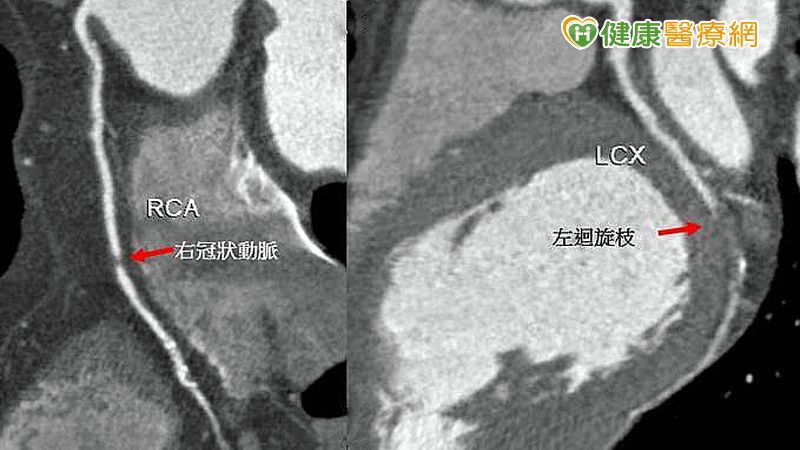

▲52歲男性企業家,經電腦斷層血管攝影檢查,顯示右冠狀動脈及左冠狀動脈迴旋枝均有小段完全阻塞外(箭頭),左前降枝也有一長段呈現阻塞(箭頭),經心導管檢查及支架置放術後,迅速康復。冠狀動脈性猝死(sudden coronary death)較為常見,多鑒於30~49歲的人,男性比女性多3.9倍